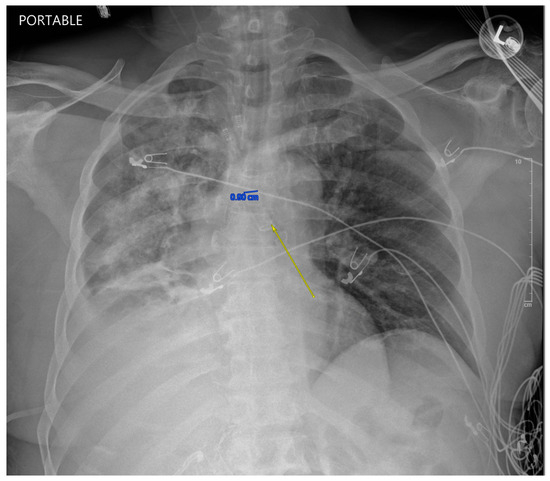

While in the MICU, the patient was weaned off pressors, and IP conducted another bronchoscopy, which showed thick, bloody secretions in the right lower lobe airway. There were no obvious secretions in the left airway. Therapeutic suctioning was performed. The patient remained intubated during post-operative day one and was started on a five-day course of Zosyn given the acute infiltrations seen on chest X-ray in the right lung (see Figure 2). Bile cultures were negative. The patient was extubated on post-operative day two with the difficult airway team present. The patient was alert and oriented to person, place, and time with appropriate biliary drain function (200 cc/day) and ambulating with assistance (ICU mobility level 8). In April 2024, the patient underwent a staging cholangiogram with internalization of the biliary drain (see Figure 3). Finally, the patient underwent a successful embolization of the biliary-pleural fistula in March 2024.

Figure 2. AP chest X-ray demonstrating DLT and infiltrated right lung with preservation of the left lung on admission to MICU. The yellow arrow demonstrates left bronchus intubation and a protected left lung compared to a patchy and opaque right lung from bilious contents entering the right airway.